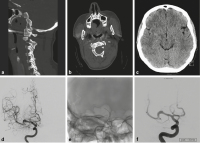

Abbildung 4a-f: Der 82-jährige Patient kam mit Kopfschmerzen zur Aufnahme. Im CT zeigte sich eine kleine Hyperdensität an der Basilarisspitze nach links (a). Eine Lumbalpunktion erbrachte xanthochromen Liquor. Die Angiographie zeigte eine dolichoektatische Erweiterung der linken A. vertebralis und der A. basilaris mit einem fusiformen Aneurysma des linken P1-Segmentes (b). Es wurde ein flusskorrigierender Stent implantiert (c, d). In der Jahreskontrolle (e) ist das Aneurysma rückgebildet und die MR-Angiographie 5 Jahre nach der Behandlung (f) ergibt keinen Anhaltspunkt für ein Rezidivaneurysma. Auch die dolichoektatische A. basilaris zeigte einen stabilen Verlauf.